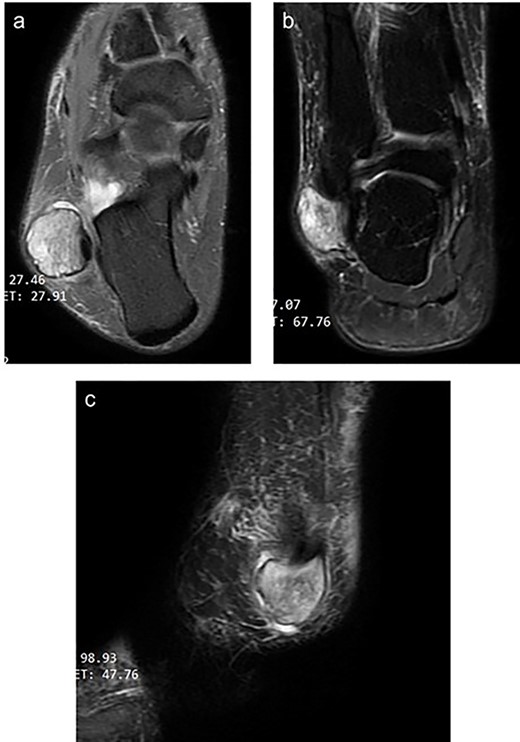

An AP, lateral & oblique X-ray views of her ankle were unremarkable for any boney or articular abnormalities. MRI with intravenous contrast showed a peroneus longus intra-tendinous ganglion cyst that measures 25*20 mm below the lateral malleolus with a thin wall (Fig. 1). The cyst contains fluid and fine septation within—a fine marginal mass enhancement after contrast uptake. The tibialis anterior and the Peronei tendons sheath showed tenosynovitis.

Magnetic resonance image of the right ankle (a: T2-weighted axial view b: T2-weighted coronal view c: fat-saturated T2 weighted sagittal view) showing a thin-walled well-circumscribed lesion within the peroneus longus tendon.